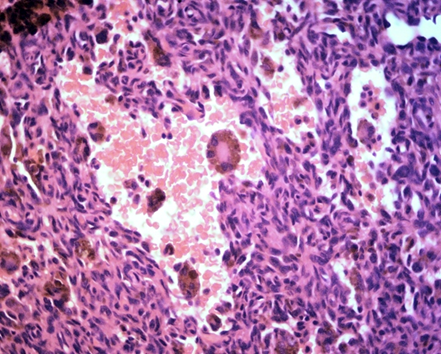

Figure 5&6 fibrohistiocytoid neoplasia, with giant cells containing brownish pigmentation suggestive of hemosiderin, cracks without vascular endothelium, containing red blood cells inside.